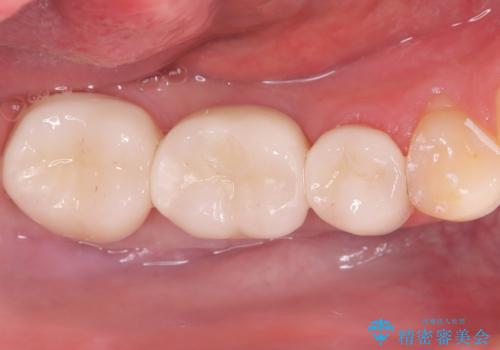

「つながった歯を独立させ、清掃性と耐久性を向上。インプラントとFGGによる機能再建」

インプラントとセラミック修復: 中央の6番にインプラントを埋入し、両隣の5番・7番はそれぞれ独立したセラミッククラウンで修復しました。ブリッジ時代は歯がつながっていたためお手入れが困難でしたが、個別の歯になったことで、一本ずつフロスが通るようになり、セルフケアの精度が劇的に向上しました。